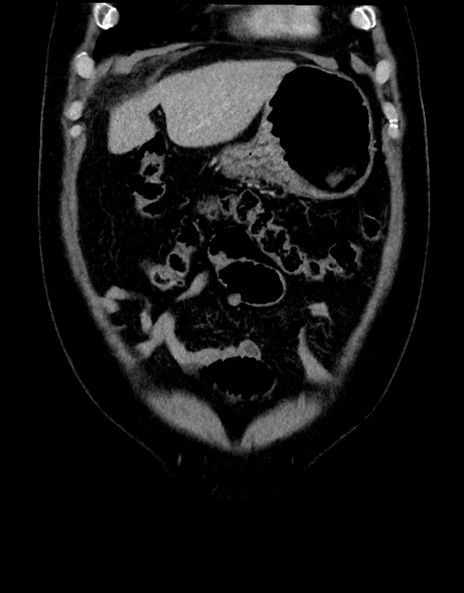

症例15(冠状断像)

【現病歴】今朝から腹痛あり。全体的に痛い。特に左上の方。排ガスが今日はない。冷や汗が出る。

【既往歴】直腸癌術後

【身体所見】左側腹部〜上腹部に圧痛あり。腹膜刺激症状明らかなではない。軽度反跳痛。左下腹部に術後瘢痕あり。

横断像